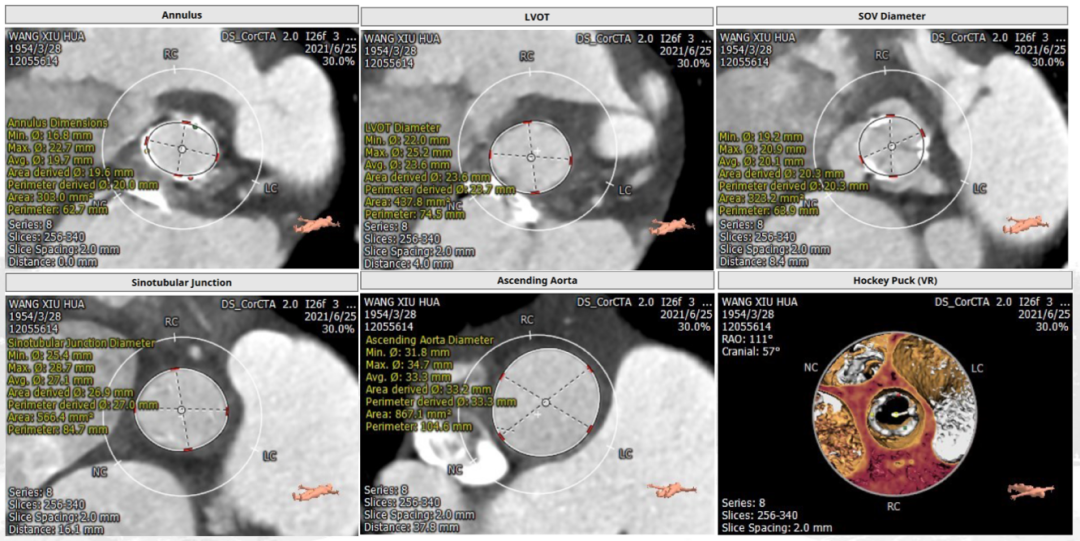

CT评估:

(一)主动脉瓣位评估:

左心耳无血栓,perimount 21瓣膜瓣环,左室流出道,窦管交接区,升主动脉评估,心室大小,全主动脉入路评估,冠脉风险评估,详细见下图。

1. 基本层面CT评估(图1)